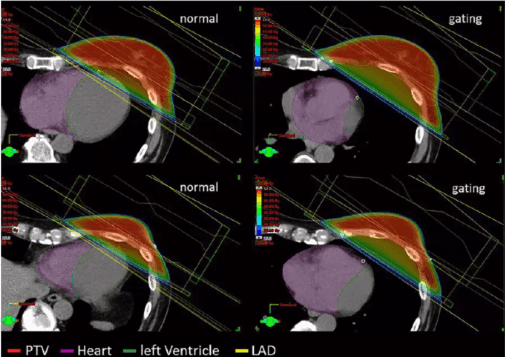

03a - Atemgating bei Mammakarzinom/Brustkrebs

Was ist Atemgating? Eine Methode in der Strahlentherapie, bei der die Bestrahlung gezielt in einer bestimmten Atemphase (z.B. bei tiefer Einatmung) erfolgt, um Organbewegungen zu berücksichtigen und gesunde Organe besser zu schonen

Wie funktioniert es? Die Bestrahlung wird nur in exakt definierten Atemphasen durchgeführt, was durch Sensoren und spezielle Software überwacht wird. So wird eine millimetergenaue Bestrahlung ermöglicht

Wofür wird es eingesetzt? Besonders häufig bei Brustkrebs, Lungenkrebs, Leber- und Magentumoren, weil sich diese Organe beim Atmen bewegen

Welche Vorteile bietet es?

Weniger Nebenwirkungen, da weniger gesundes Gewebe bestrahlt wird.

Höhere Effizienz und Präzision der Behandlung.

Besonders bei linksseitigem Brustkrebs: Herz und Lunge werden deutlich besser geschützt

Fazit: Atemgating erhöht die Präzision der Strahlentherapie und reduziert die Belastung gesunder Organe deutlich.

- Ein Gating-System der Firma Varian ausgestattet mit einer 3D-Kamera: Dank der atemgetriggerten Bestrahlung können wir die Strahlung genau dann auslösen, wenn die maximale Schonung von Herz und Lunge gewährleistet ist.